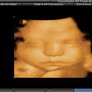

A 3D ultrasound, which uses high-frequency sound waves & special imaging software to provide incredibly clear images of your baby,can be done at any point in pregnancy.While 3D ultrasounds are becoming more common,there's really no medical benefit to having one for most women,so you may or may not be offered one as part of your routine prenatal care.